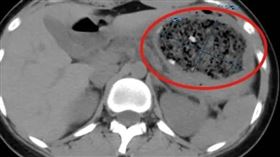

「1水果」害他腸穿孔!緊急切除後才保命

水果有益健康,但要小心可能造成胃腸結石,引發腸阻塞。...

女大生狂嗑1斤山楂胃長巨石 靠1飲品痊癒

近日中國一名19歲的大學二年級學生倩倩(化名)因食用...